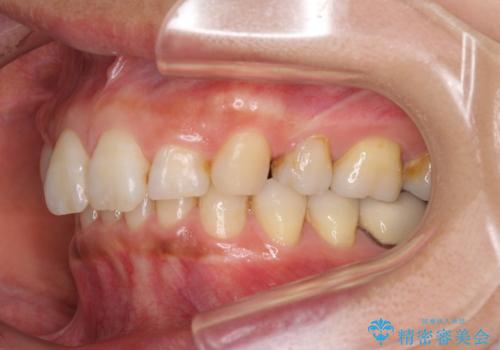

抜歯矯正の後戻りでできたスペース インビザライン矯正とセラミック治療

- 以前行った抜歯矯正が後戻りし、開いてしまったスペースが気になるとのことで来院された患者様です。

インビザラインを用いて開いてしまったスペースと前歯のデコボコを改善することとしました。

矯正治療後には気になっていた銀歯をセラミッククラウンやセラミックインレーにて治療することとしました。

上顎前歯を左右対称となるように歯列を整えたいとのことでしたが、すり減って形態が大きく異なっていたため、できる範囲での仕上がりとなりました。